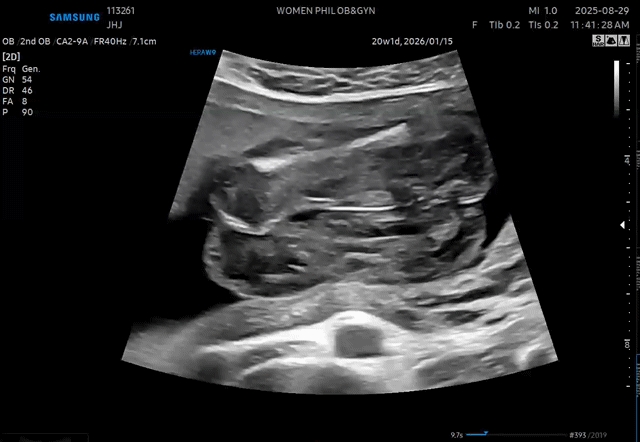

어제 20주맞이해서 정밀초음파 봤습니다 애기가 다리를 오므리고 있어서 성기는 잘 안보인다고 하는데... 정밀초음파 봐주신 선생님+진료봐주신 선생님 둘다 '자세때문에 잘 안보이지만 딸같네요~' 했는데 딸 확정일까요?!? 혹시라도 결과 반전있을까봐 (갑자기 24주에 갓는데 꼬츄가 보인다던가......) 뭔가 찝찝?합니다 ㅋㅋㅋㅋ 속이 시원하지못해요 여러분들 보시기는..어떱니까 ㅠㅠ

이때 아들이라면 아주 뚜렷하게 보인대요~~~ 뚜렷하지 않으니 딸일거 같네요 ㅎㅎ

딸같은데요??